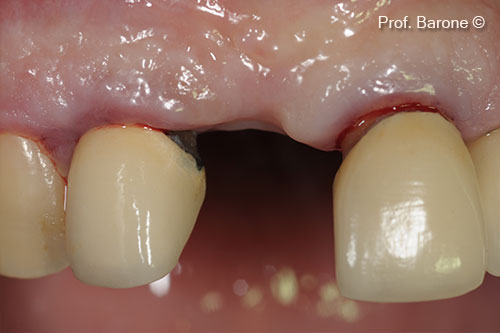

Healing after 3 months

Augmented Ridge